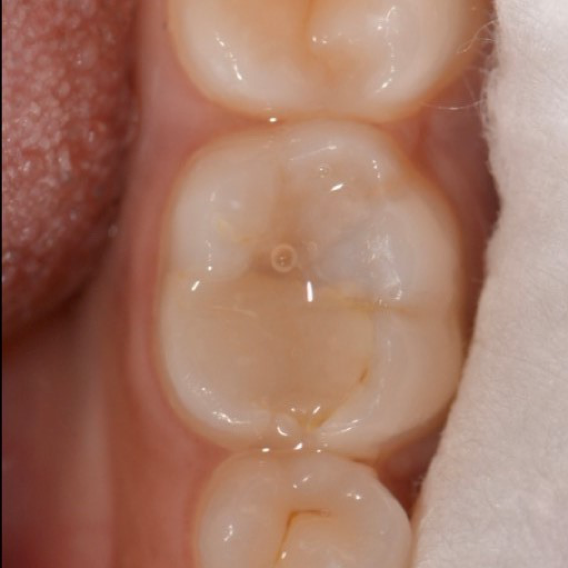

Fig 10. Immediate post operatory

With a series of different finishing burs, the occlusal surface was finished and polished (Figure 10). The occlusion was verified. The occlusal surface was then smoothed with polishers and the restoration was polished with polishing paste. Post-operative radiograph revealed the extent of Predicta due to its excellent radiopacity (Figure 11).

During the follow up period of four months, the restoration showed no unfavorable events. It displayed excellent quality with no marginal failure. No signs of gingival inflammation or increased plaque accumulation was observed. After four months the restoration showed a satisfactory clinical performance considering patient with high caries index (Fig. 12).

Fig 12. 4 months follow up